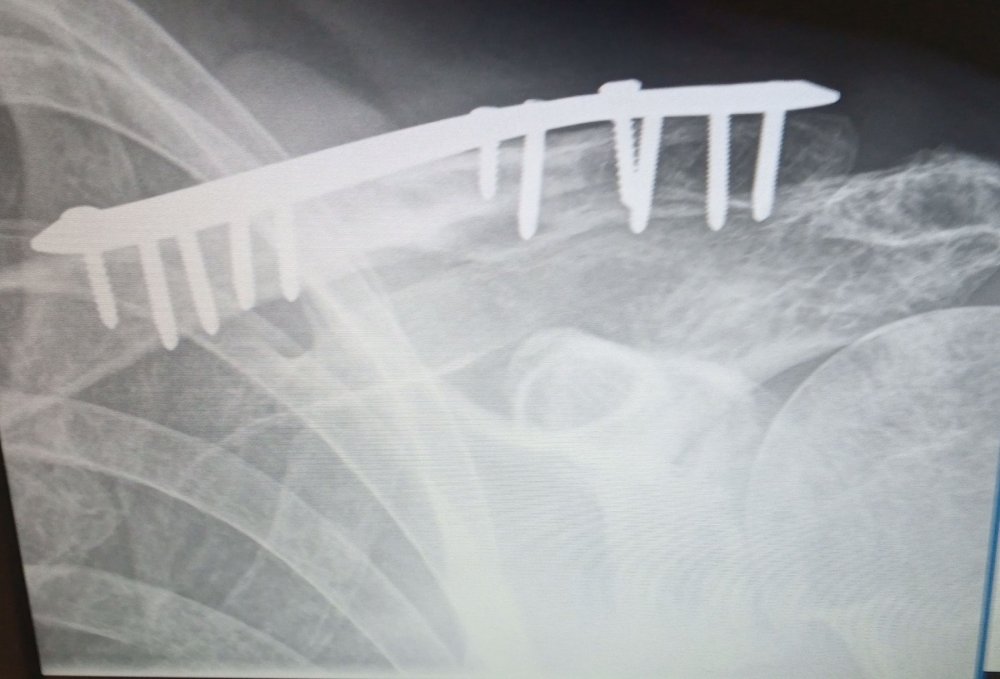

I will see your squishy fingers and raise you a broken collar bone , cycling to work before x mas and a fly went in my ear causing me to lose control and hit a hedgerow at about 20 mph .OOh that hurt ! turns out i broke my collar bone in 2 places needing 11 pins